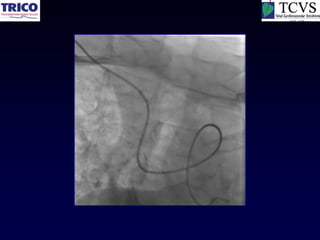

Catheter Knot

Reduction

Another example